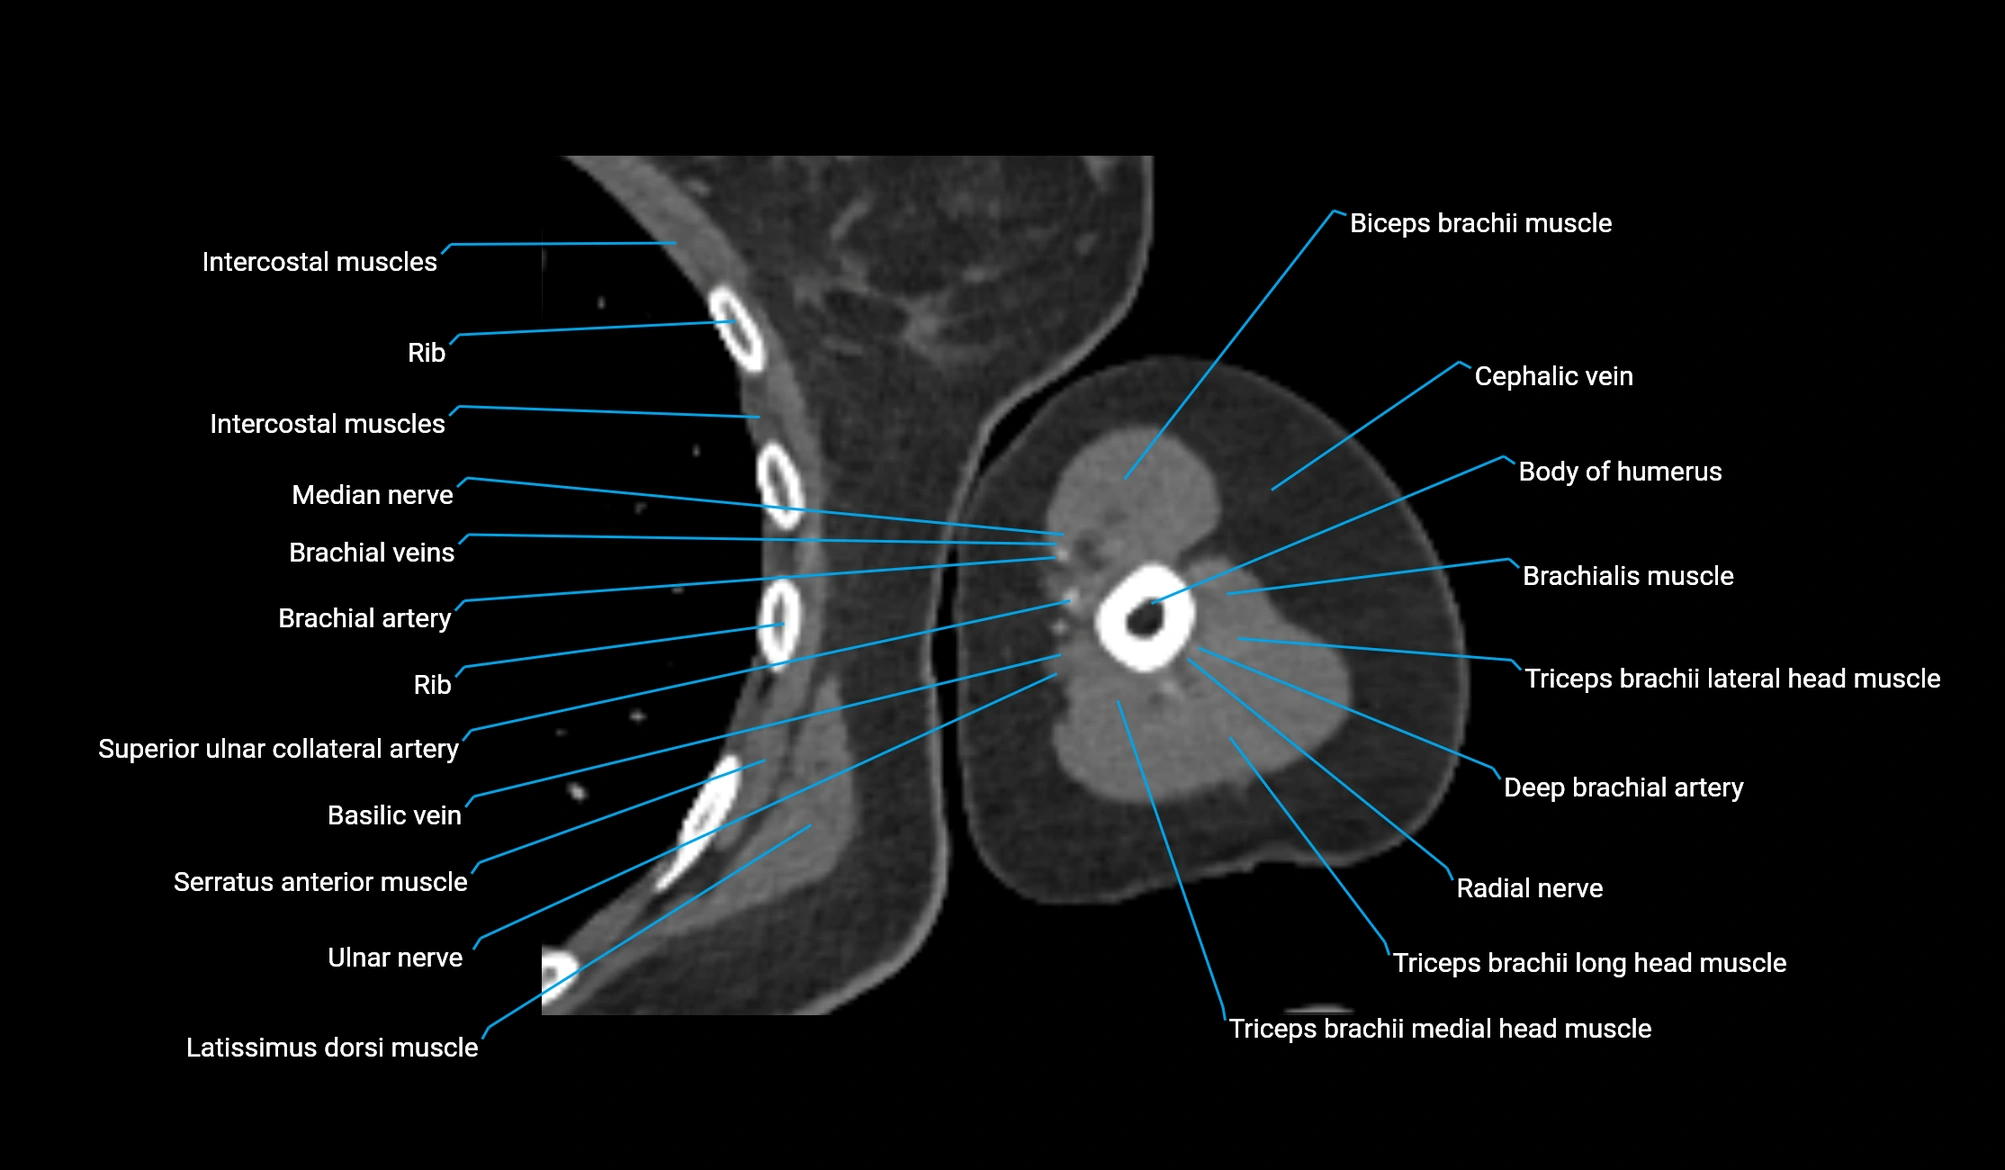

- Body of humerus

- Brachial artery

- Brachialis muscle

- Cephalic vein

- Deep brachial artery

- Long head of triceps brachii muscle

- Medial head of triceps brachii muscle

- Median nerve

- Radial nerve

- Superior ulnar collateral artery

- Ulnar nerve